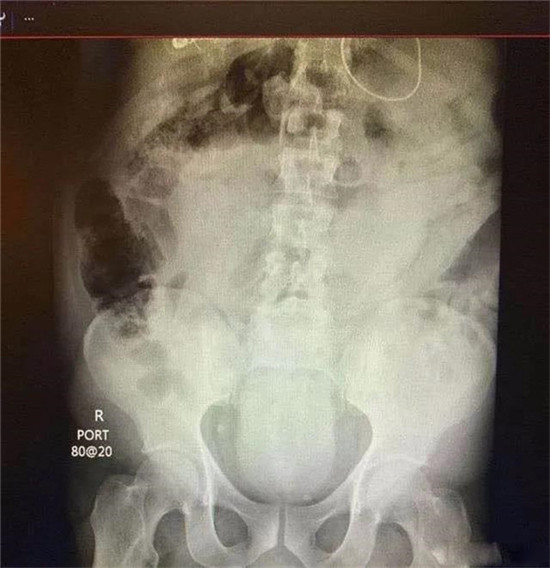

医生给他检查的时候,发现已经有腹膜炎症状,怀疑肠梗阻,拍了个片子,就是上面那个片子:一条大黄鳝在肚子里。

考虑到他已经有腹膜炎的症状,说明肠子已经有个地方破了。只能动手术了。

把肚子打开后,发现大肠破了个洞,黄鳝的头,就在那个洞里。他肚子里都是大便。他的肠子水肿很厉害。黄鳝堵住了大肠,肠梗阻,导致大肠坏死穿孔了。

这种情况下,就是把大肠的洞补起来,洞也长不好。只能造瘘了。也就是在破了个洞的地方把大肠割断,肚皮上挖个洞,大肠拖到肚皮外面,以后的大便从肚皮上排出来。等肚子里炎症消退后,再把大肠放回肚子里接回去。这样他要动2次手术。

就这样,他死里逃生了。